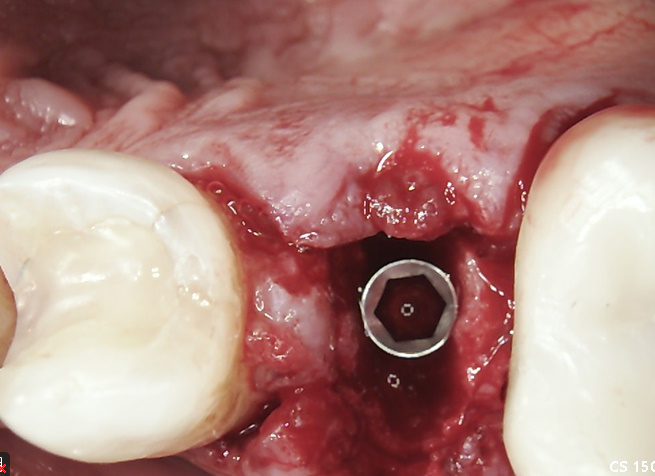

Practical case with DSI Premium Spiral Implant